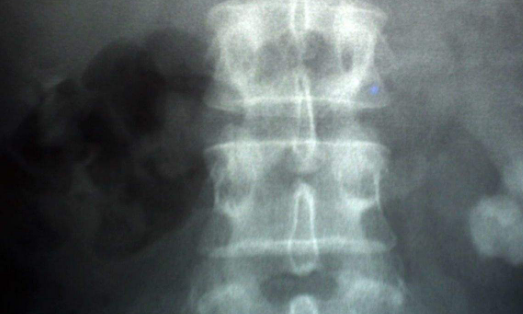

输尿管结石的治疗方法二:体外震波碎石采用x线定位的dornier型机治疗,已由上段输尿管结石扩大到输尿管中、下段结石。上段输尿管结石宜采用斜侧半卧位,对于髂骨翼重叠部位的结石应采用俯卧位;下段可采用半坐位,提高电压,均可取得一定的成功率。虽然输尿管全长各部位的结石可用体外震波粉碎,但在结石较小、体胖患者有时存在定位困难,部位深、耗能多等问题,与粉碎肾结石比较,粉碎输尿管结石的难度相对较高,总的效果比肾结石差。因此,必须加强震波时的定位准确性,有困难者同时作排泄性尿路造影或做膀胱镜逆行插管与造影,以协助定位。如能将结石推入肾盂再行震波,则最为理想。

输尿管结石的治疗方法三:手术切开取石适应证是:①输尿管存在狭窄者;②双侧或单侧输尿管结石嵌顿伴感染引起尿闭者;③结石较大,肾积水严重,肾功能很差者;④体外震波不能定位或震波失败者;⑤临床不能除外肿瘤或结核;⑥经济因素。手术前2小时须拍尿路平片定位。 如为女性输尿管下段较大结石,有时经阴道穹窿部检查触及结石,经按摩使结石排出。